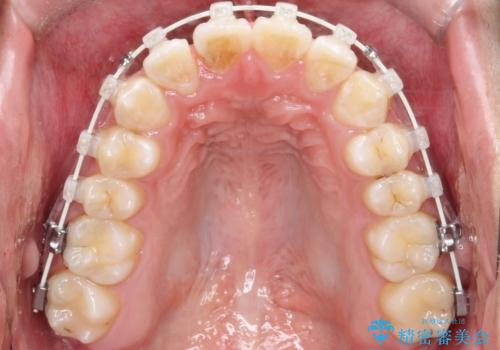

- 矯正装置

- 審美装置

【ワイヤー矯正】前歯の凸凹を治したい。

- 前歯の凸凹を主訴に来院されました。

患者様がマウスピース矯正の使用時間に不安があるため、ワイヤー矯正にて治療を行なっております。